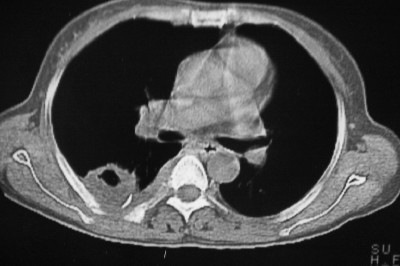

以下是引用天南地北在2007-4-10 1:49:00的发言:[br]考虑右下叶周围型肺癌伴肋骨转移。

以下是引用jone-baby在2007-4-10 8:45:00的发言:[br][br] [br] 患者[br]有发热史,x线片考虑肺脓肿.肺脓肿可以导致肋骨破坏吗?[br]脓肿可以排除吗? [br] [br] [br]

以下是引用林建春在2007-4-10 7:35:00的发言:[br]周围型肺癌侵犯肋骨

以下是引用liuyue在2007-4-10 7:56:00的发言:[br]周围型肺癌侵犯肋骨,左肺转移。

以下是引用zhangzhongshou在2007-4-10 10:24:00的发言:[br]右肺下叶背段厚壁空洞,伴胸膜改变、肋骨破坏,其内可见死骨、周围骨质硬化,左肺可见小结节影,[br]单纯影像学更支持结核。建议进一步检查。